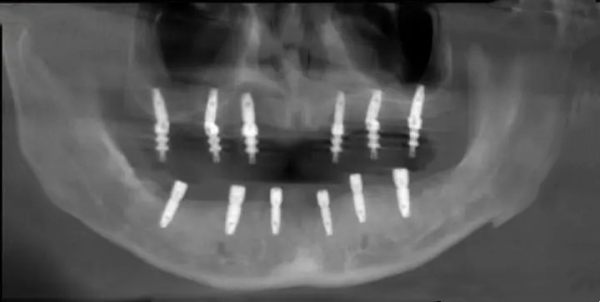

• 德國卡瓦(KaVo)三維CBCT:高清掃描頜骨結(jié)構(gòu),穩(wěn)準(zhǔn)評估骨高度、密度及神經(jīng)位置

• 瑞典NobelGuide數(shù)字化種植導(dǎo)航系統(tǒng):術(shù)前模擬種植路徑,術(shù)中實(shí)時(shí)引導(dǎo),誤差控制在0.1mm以內(nèi)

• ALL-ON-4/6即刻負(fù)重技術(shù):僅需4–6顆植體即可支撐整排牙齒,當(dāng)天種牙當(dāng)天吃飯